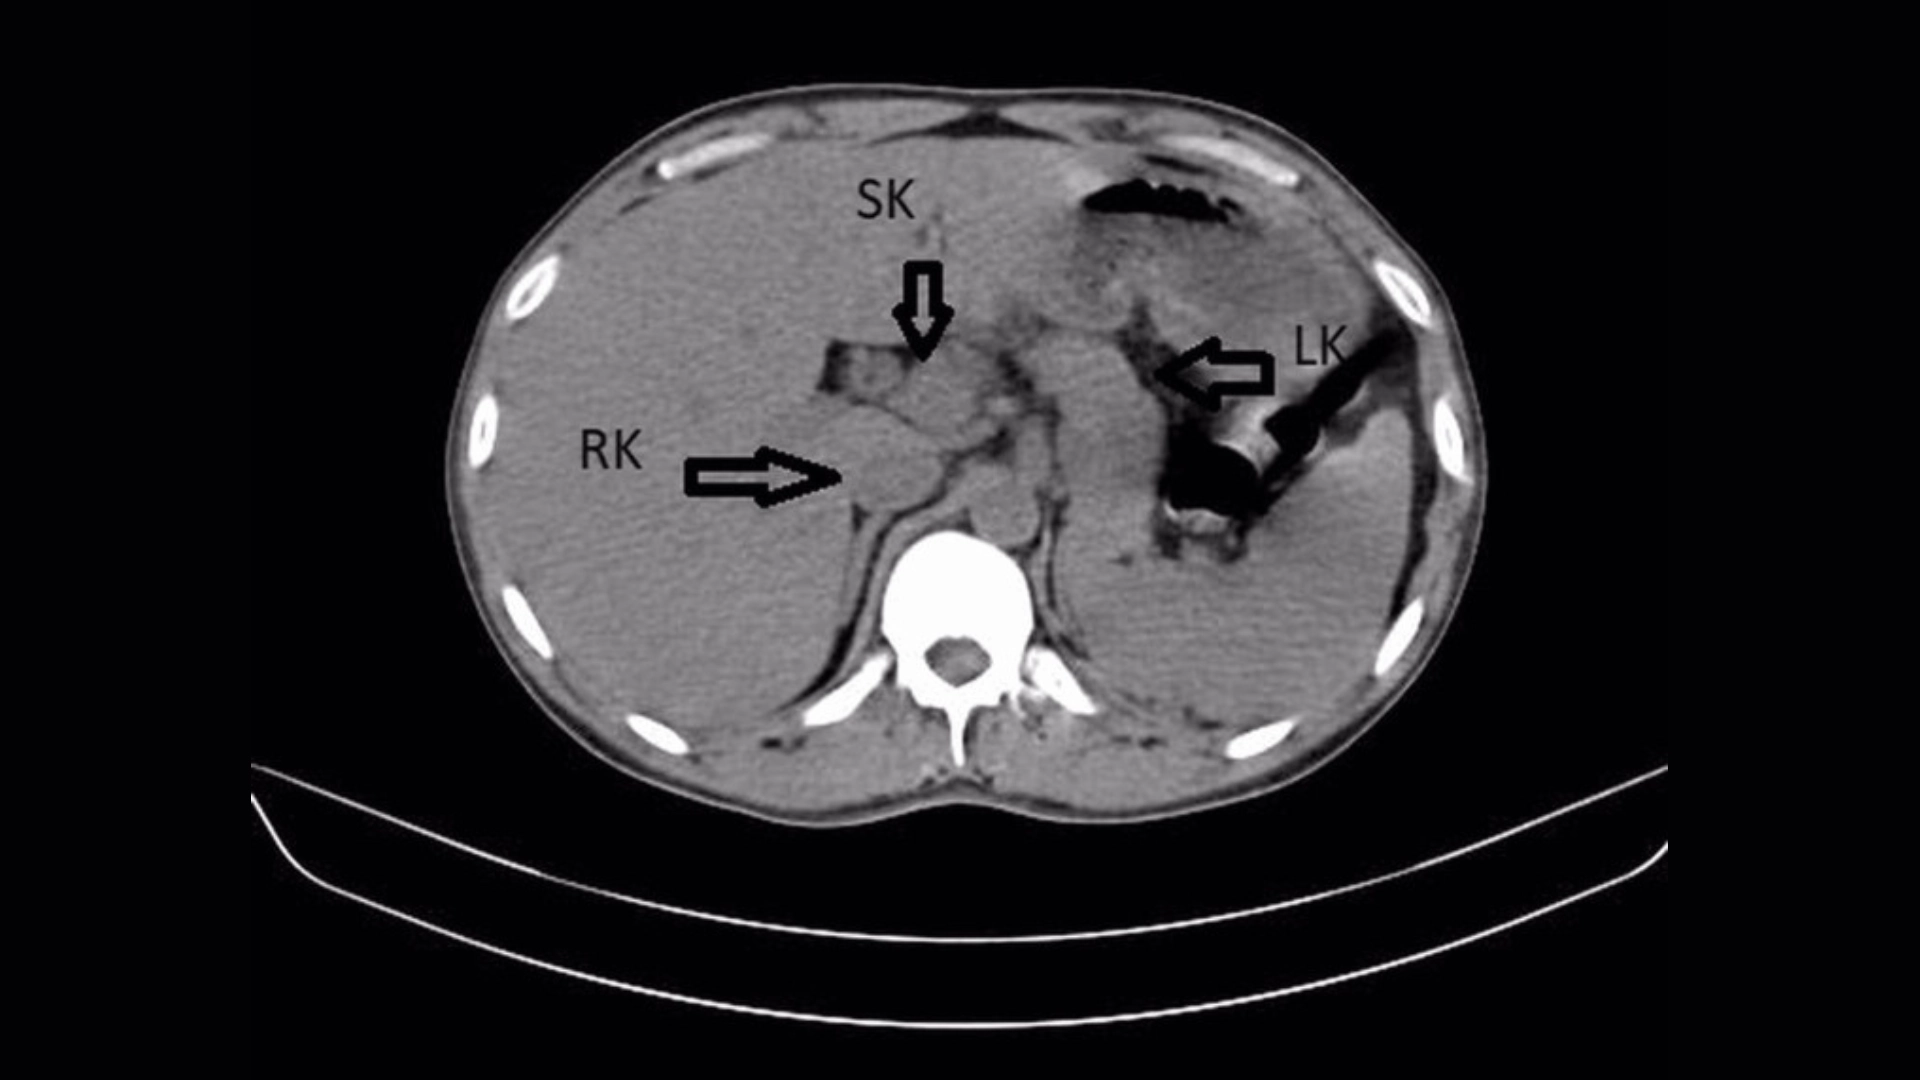

But in addition, an ultrasound and a CT scan of the patient's abdomen revealed something unexpected: a third kidney, also known as a supernumerary kidney. It was fused to the man's right kidney, creating a horseshoe shape.

A supernumerary kidney is a congenital anomaly that is thought to emerge during fetal development. It appears due to abnormal cell division in the cord that later forms the kidneys. A supernumerary kidney can sometimes lead to kidney infections, but the condition does not always affect normal kidney function and often goes undetected, according to the report.

In this case, the patient's left and right kidneys were swollen and showed accumulations of calculus, or mineral crystals. These hard crystals form when urine is more concentrated; small "stones" often pass normally during urination, but can lead to infection if they linger untreated in the kidneys.

The signs of infection were more serious in the left kidney, with calculus buildup in the left ureter, the tube that connects the left kidney to the bladder.

A fused "horseshoe" appearance with another kidney is even rarer, with only five cases reported in the scientific literature. Third kidneys can also be completely separate or loosely connected to another kidney by a thin layer of tissue.